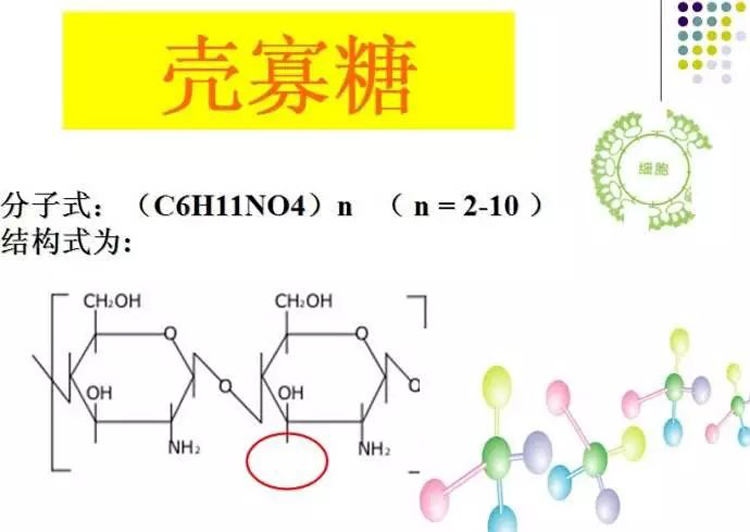

Chitosan oligosaccharide, derived from chitosan through hydrolysis, has several versatile applications owing…

Chitosan oligosaccharide (COS) is a bioactive compound derived from chitosan, which in…

Chitosan oligosaccharide is a natural compound derived from chitosan, which comes from…